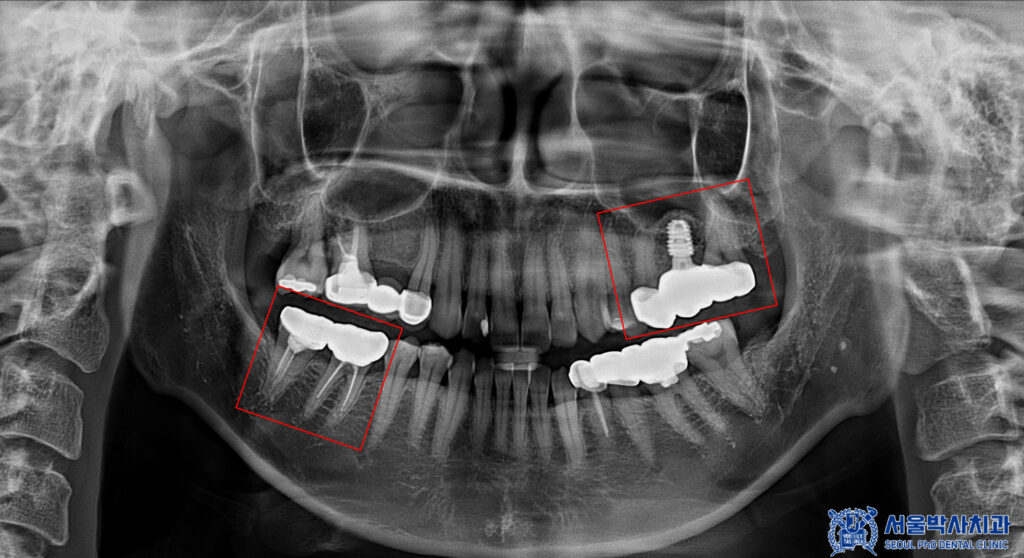

파노라마 촬영으로

전체 상태를 먼저 확인했습니다.

다만 크라운은 방사선 불투과성이 있어

내부 평가가 제한되므로,

정밀 엑스레이를 추가로 촬영해

보철물 하방 상태를 점검했습니다.

그 결과, 브릿지 아래쪽에

우식이 진행된 것이 확인되었습니다.

이에 신흥동치과 서울박사에서는

위쪽 브릿지를 모두 제거하고,

지대치는 크라운으로 다시 보철하며

인공치가 있던 부위는

임플란트 식립을 진행하기로 했습니다.

아래쪽 보철 역시 제거 후 상태에 맞춰

재보철을 진행하는

계획으로 안내드렸습니다.